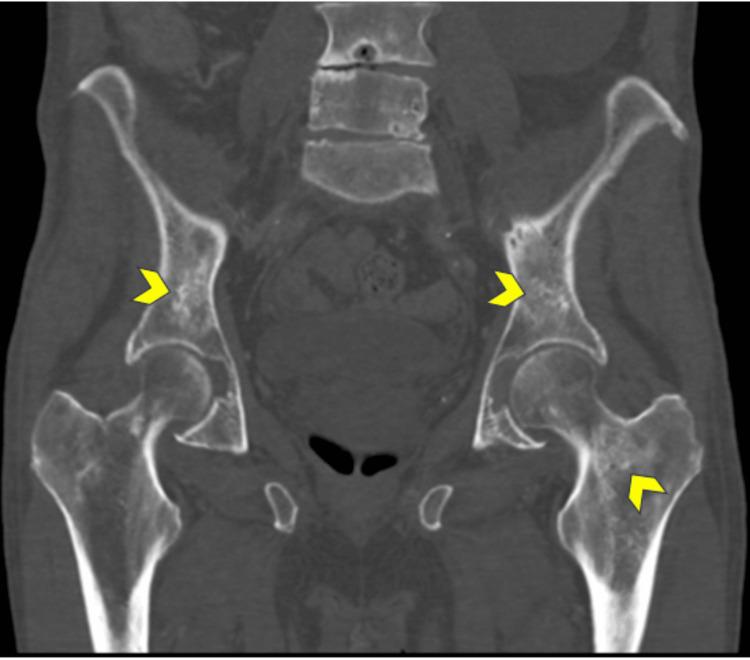

Erdheim-Chester disease (ECD) is a rare, multisystemic, non-Langerhans cell histiocytic neoplasm predominantly affecting middle-aged males in their fifth to seventh decades of life. It often presents with nonspecific symptoms, leading to a delay in its diagnosis. We report a case of an 85-year-old male with multisystemic manifestations, including retroperitoneal, skeletal, vascular, cardiac, orbital, and central nervous system (CNS) involvement. Imaging revealed characteristic findings such as bilateral osteosclerosis, perirenal infiltration (hairy kidney sign), and dural-based intracranial masses. Histopathological analysis confirmed the diagnosis, identifying CD68+ histiocytes and the BRAFV600E mutation. The patient was managed initially by Internal Medicine and later referred to Hemato-Oncology for further treatment. This report highlights the importance of maintaining a high index of suspicion for this rare disorder, as well as adopting a multidisciplinary approach toward its treatment, integrating clinical, radiological, and histopathological data.

Erdheim-Chester病(ECD)是一种罕见的、多系统的、非朗格汉斯细胞组织细胞肿瘤,主要影响50至70岁的中年男性。它常表现为非特异性症状,导致诊断延迟。我们报告一例85岁男性,有包括腹膜后、骨骼、血管、心脏、眼眶和中枢神经系统(CNS)受累的多系统表现。影像学检查发现了特征性表现,如双侧骨硬化、肾周浸润(毛肾征)和硬脑膜下颅内肿块。组织病理学分析确诊,发现CD68+组织细胞和BRAFV600E突变。患者最初由内科处理,后来转诊至血液肿瘤科进行进一步治疗。本报告强调了对这种罕见疾病保持高度怀疑指数的重要性,以及采用多学科方法进行治疗,整合临床、放射学和组织病理学数据。